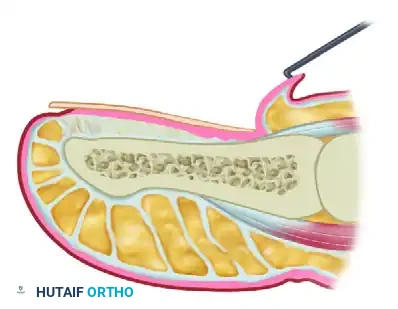

Step 3: Elevation of the Eponychial Flap

Using fine skin hooks or delicate forceps, the eponychial flap is reflected proximally. This maneuver exposes the entire germinal matrix.

It is critical to differentiate the germinal matrix from the sterile (dormant) matrix. The germinal matrix typically appears as a thicker, slightly more opaque, and often protruding tissue layer beneath the eponychium, whereas the sterile matrix is thinner and firmly adherent to the periosteum of the distal phalanx. In cases of chronic onychomycosis, the dormant matrix may appear abnormal or damaged by the mycotic process.

Step 4: Excision of the Germinal Matrix

This is the most critical step of the procedure. A transverse incision is made at the junction of the germinal and sterile matrices (the distal border of the lunula). The germinal matrix is then sharply dissected off the underlying periosteum of the distal phalanx, working proximally.

Surgical Pitfall: The lateral horns of the germinal matrix curve deeply into the proximal-lateral corners of the distal phalanx. Failure to aggressively curette or sharply excise these hidden recesses will guarantee the formation of postoperative spicules.